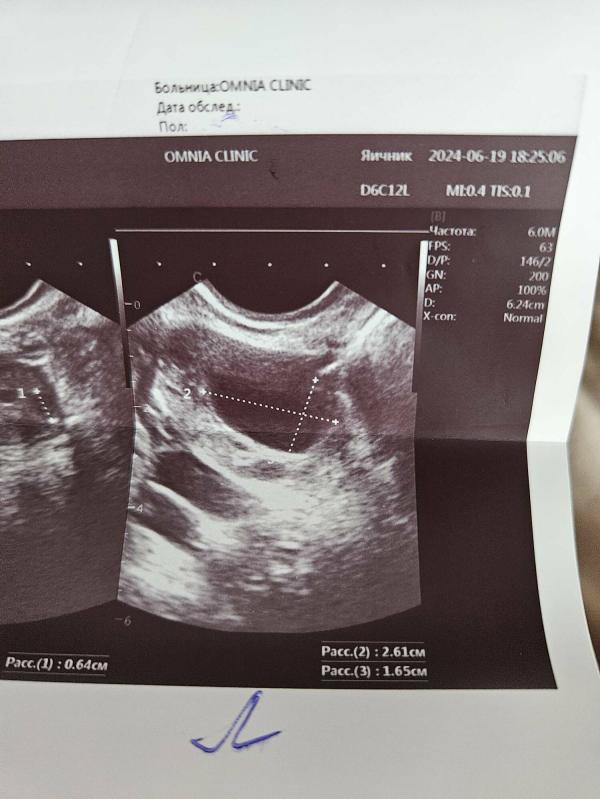

Может кто сталкивался, вчера был 15дц, ходила на фолликулометрию. В левом яичнике дф 26×16, на фото он овальный, проблем с овуляцией никогда не было и вообще первый раз вижу у себя такой фолликул. Есть шансы в этом цикле? Или уже перерастет в кисту?